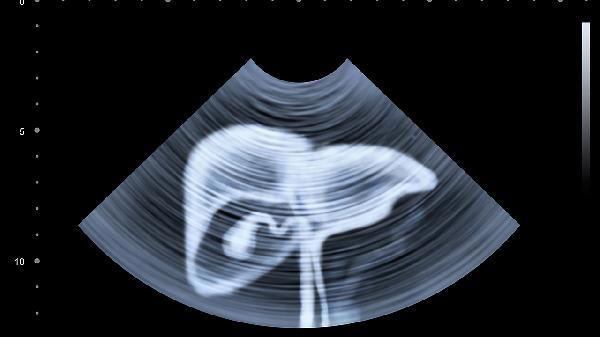

脂肪肝已经成为现代人的"标配"疾病,很多人拿到体检报告时才发现自己中招。别以为这只是个小问题,如果不及时干预,可能会发展成更严重的肝病。其实,调整饮食就能让肝脏"减负",特别是这4类食物,一定要从餐桌上撤下来!